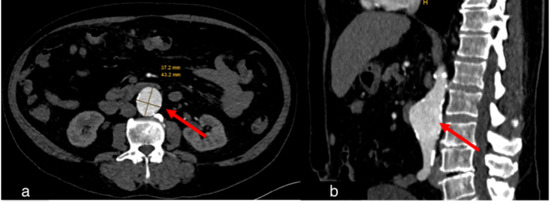

Figure 4.

Case 1, a 67-year-old female. (a) Initial chest CT to clarify pulmonary embolism or post-COVID-19 findings showed concentric wall thickening of the thoracic aorta (red arrow), indicating large vessel vasculitis. No pulmonary infiltrates or post-COVID-19 findings were observed. (b) Follow-up computed tomography 2 months later showed indeterminate appearance of recurrent COVID-19 pneumonia (blue arrow) and regressed arterial wall thickening (red arrow).